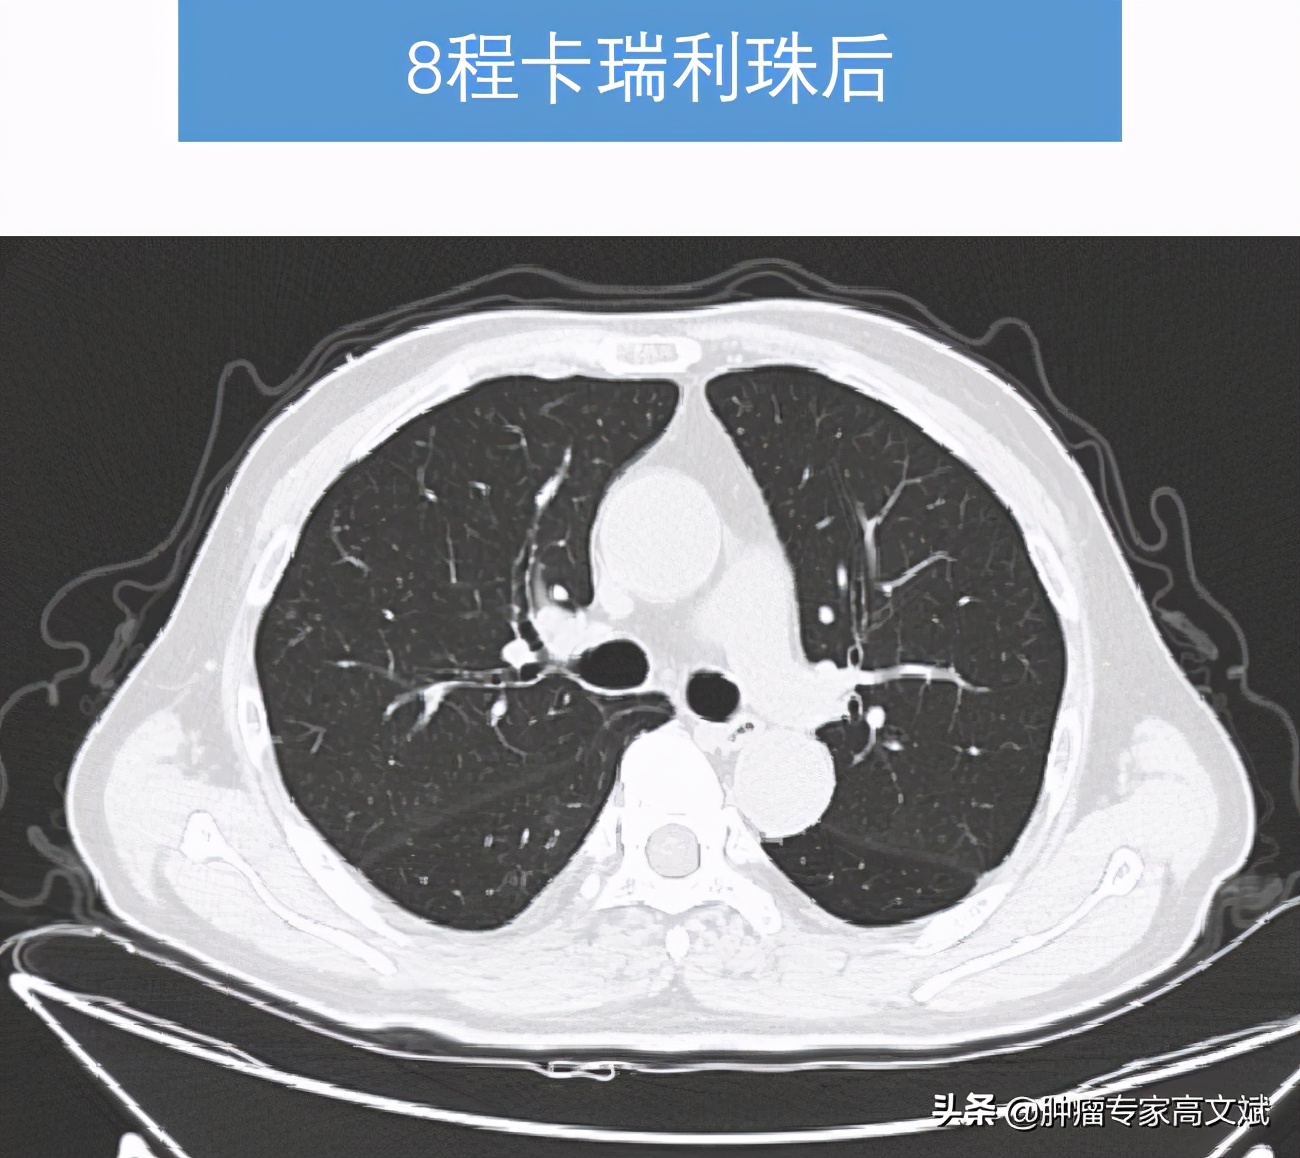

看着患者的一般情况还好,所谓的身体状况不佳主要还是前边治疗的不良反应所导致的。我们还是决定给患者实施一个单药的免疫治疗来控制肿瘤的生长,又不过分增加患者的不良反应。就这样患者也接受了我们的建议,我们为患者实施了国产的免疫制剂卡瑞利珠单抗(艾瑞卡)200mg,每2周一次使用。让我们没有想到的是,患者治疗2个周期以后,肿瘤标志物AFP出现了陡坡样的下降,肝脏疼痛也出现了缓解,每天躺在床上的老陈已经开始下床活动,饮食量等情况也明显的改善,对于治疗患者也有了明显的信心。就这样,治疗了8个周期以后,老陈的肝脏肿瘤明显缩小了,肺内转移灶也有消失,肿瘤标志物则是更早地恢复了正常,止痛药也完全的不再使用了。对于老陈来说,剩下的事情就是每月来罗湖医院肿瘤科输注两次卡瑞利珠单抗(艾瑞卡)就可以了。